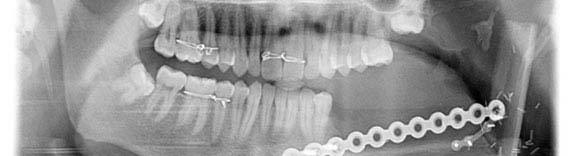

Microvascular Recontruction of the Jaws

The cancer of the oral cavity are quite common now a days. The surgical treatment leaves the patient with poor quality of life in the post operative phase. At our institute cancer surgeries are performed routinely and the reconstruction of the defect is done by microvascular surgery using free fibula graft, which is rarely performed in dental colleges. This ensures complete rehabilitation of the patient’s form, function and aesthetics and boosted self confidence of still being in the societal mainstream.